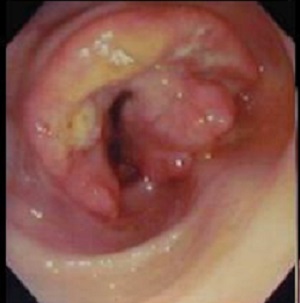

Aspect macroscopique du colonoscopie , sigmoidoscopie

et coloscopie virtuelle d'une adenome carcionoma du colon .

Aspect macroscopique de

coloscopie d'une adenocarcinoma du colon |

Aspect d'une

autre cas de adenome carcinoma du colon . Image

macroscopique d'une sigmoidoscopie |